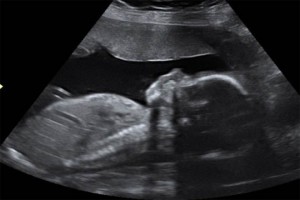

Diplomado en ultrasonografia medica

Diplomados en Ultrasonografía